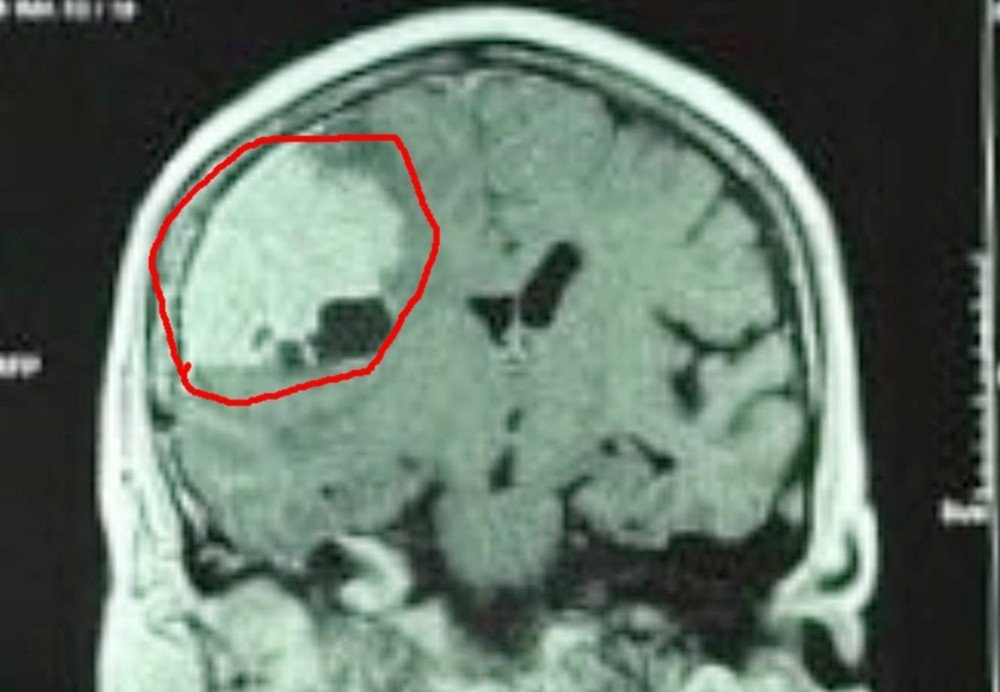

Tuy nhiên, gần đây bệnh nhân không chỉ đau đầu, mà còn thấy mệt yếu nửa người bên trái, lừ đừ tiếp xúc kém. Tại Bệnh viện Trưng Vương, kết quả chẩn đoán hình ảnh, bác sĩ phát hiện bệnh nhân bị u màng não lớn vùng thái dương bên phải, có nhiều mạch máu nuôi u.

| Khối u màng não khổng lồ là nguyên nhân khiến người bệnh thường xuyên đau đầu |

Ngoài khối u màng não kích thước lớn, người bệnh còn mắc bệnh lý mạch vành nên phải được hội chẩn trở lại bởi các bác sĩ chuyên khoa tim mạch. Các bác sĩ đã hội chẩn liên chuyên khoa tìm giải pháp can thiệp hiệu quả và quyết định thực hiện can thiệp nội mạch gây tắc mạch nuôi khối u để hạn chế máu chảy khi phẫu thuật bóc tách. Sau tắc mạch thành công, bệnh nhân sau đó đã được phẫu thuật lấy toàn bộ khối u. Hơn 1 tuần sau cuộc mổ, bệnh đã tỉnh táo, hết yếu liệt, sinh hoạt bình thường.